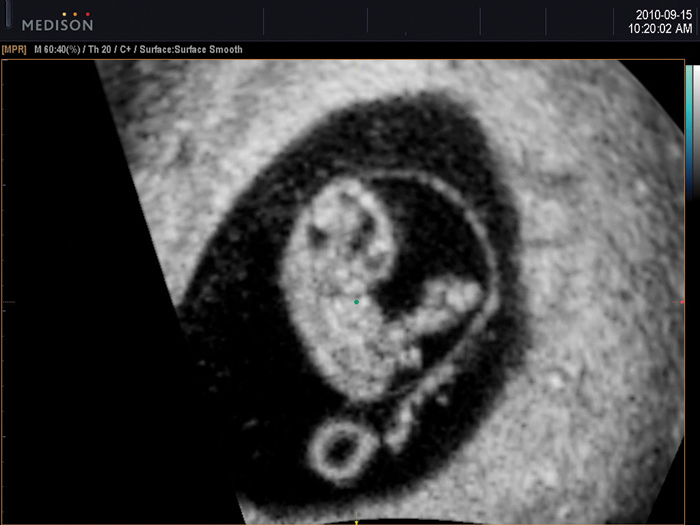

HDVI™ is based on non stationary adaptive filtering resulting in removal of unwanted speckle and noise whilst increasing visualization of edges and small structures in volume data. HDVI™ uses a 3D processing algorithm that is based on 3D matrix processing of volume data.

The essential feature of this 3D processing algorithm is matrix image processing which allows more accurate rendered information calculated from the voxel data of the acquired volume data.

By using this calculation method, a clear and improved image is shown in the rendered and multi-planar views.

HD Volume Imaging™ (HDVI™) removes artifacts and incorporates a speckle reduction filter without compromising details but at the same time emphasizing the edge and structures. Therefore, 3D rendered image and multi-planar view provides an image quality with improved contrast and resolution. According to the result, it shows that the speckle noise of the image with HDVI™ is lower while the edge enhancement are higher, compared to the Original.